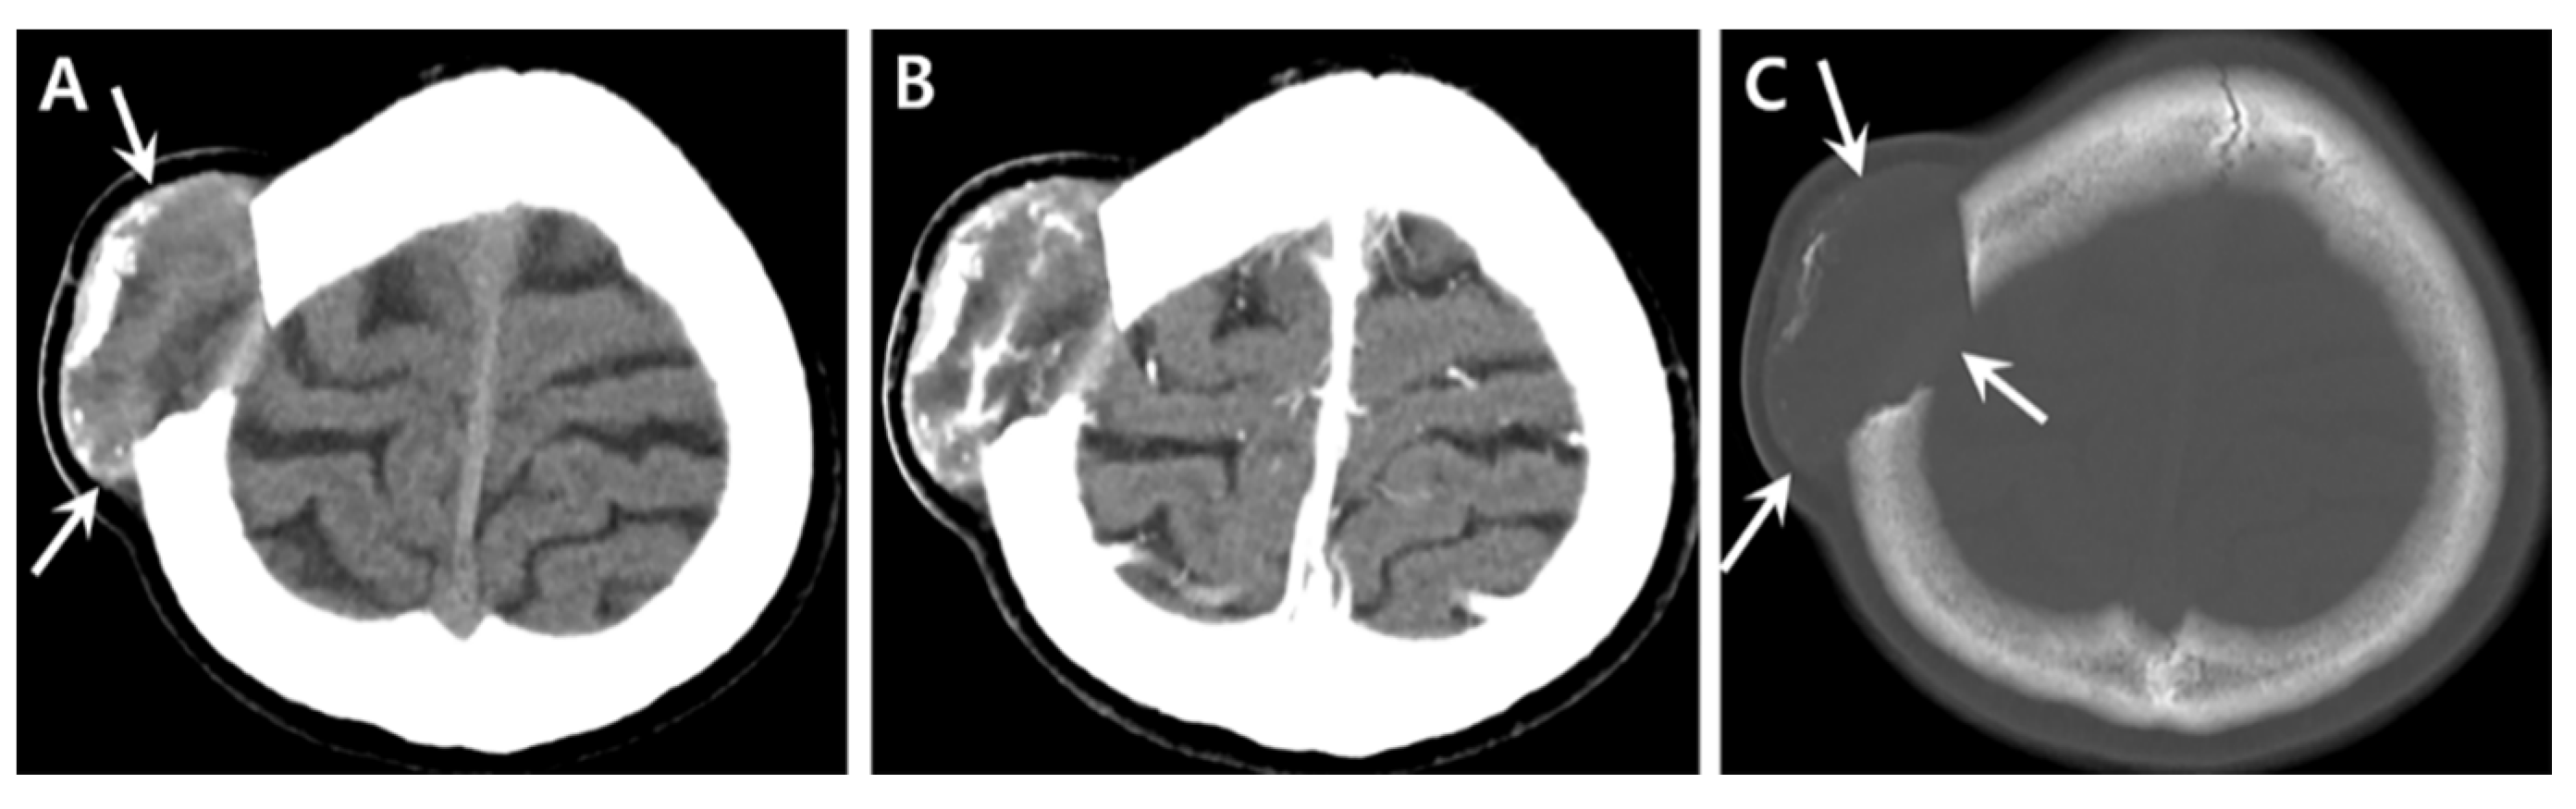

Chronic Intradiploic Organizing Hematoma of the Skull Mimicking Calvarial Tumor Diagnosed Using Zero TE MRI: A Case Report and Review of Literature

2. Case Report